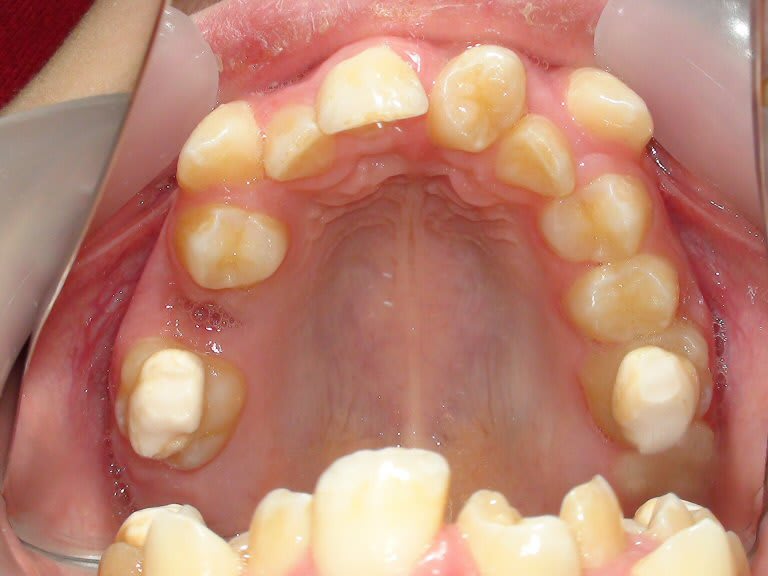

Cela se voit bien ça sur la vue occlusale.

Rajoutons qu'ici l'alvéole de l'incisive était confortable pour y placer une prémolaire, ce qui n'est jamais le cas pour une jeune dont les parois osseuses vestibulaires et palatines de la dent éjectée sont résorbées, comme dans le cas que je présente.

Il faudrait donc pouvoir transplanter immédiatement après le traumatisme.

Mais aussi avec un niveau optimal de développement radiculaire du greffon…

Finalement peu de cas de traumatisme sont favorables pour une transplantation.